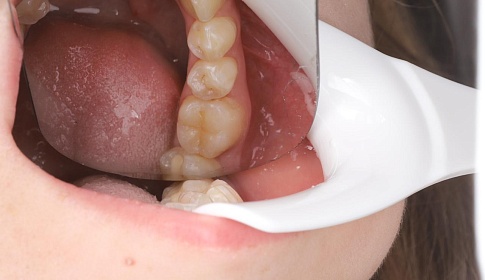

Средний

Средний кариес развивается, если не лечить заболевание на ранних стадиях. На этом этапе происходит достаточно быстрое разрушение зуба, потому что микроорганизмы достигают дентина. Зуб становится чувствительным к различным раздражителям, однако неприятные ощущения быстро проходят, стоит только раздражитель убрать. Это стадия, когда еще можно пройти лечение без осложнений. При лечении врач удалит налет, сделает анестезию, тщательно очистит и обработает пораженный участок, нанесет специальный адгезивный материал, выполнить пломбирование.